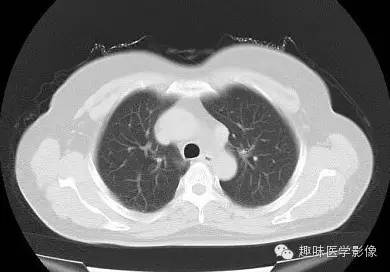

两肺未见明显异常。纵隔左侧见血管影,经主动脉弓与左肺肺门之前向下走行,汇入冠状静脉窦。

永存左上腔静脉